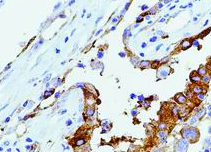

LRP抗体是一种靶向低密度脂蛋白受体相关蛋白(LRP)的免疫检测工具,该蛋白属于LDL受体家族成员,广泛参与脂质代谢、细胞信号转导及内吞作用。LRP在多种肿瘤(如乳腺癌、胶质瘤、黑色素瘤)中异常表达,其抗体可用于:①评估肿瘤微环境中LRP介导的胆固醇代谢重编程;②研究LRP作为载脂蛋白E(ApoE)受体的功能及其在阿尔茨海默病中β-淀粉样蛋白清除的作用;③检测LRP-1B等亚型在肿瘤转移和耐药性中的调控机制。该抗体在肿瘤代谢研究、神经系统疾病及心血管疾病的分子机制探索中具有重要价值。

阳性部位:

细胞质

EDTA 热修复